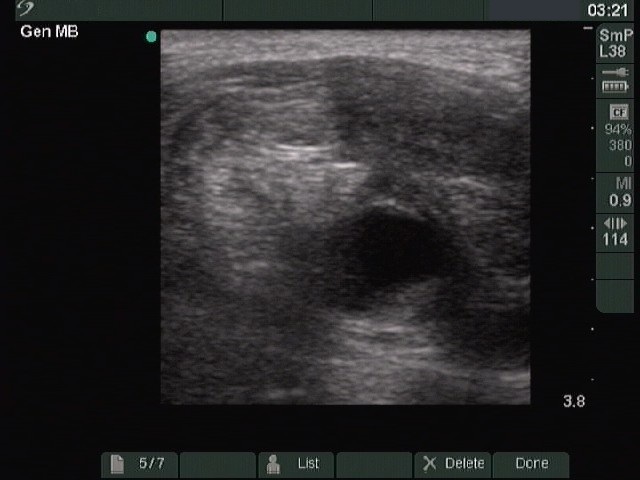

Ultrasonography. The right lobe was intact, while the left was composed of a large nodular area with multiple hypoechogenic and hyperechogenic discrete lesions. The latter corresponded to necrosis.